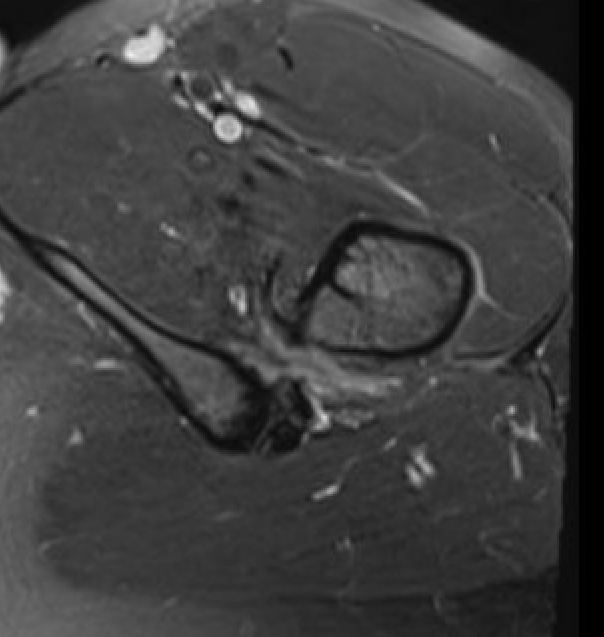

MRI

Reduced ischiofemoral space - distance between the lesser trochanter and the ischial tuberosity

Reduced quadratus femoris space - distance between hamstring tendon and iliopsoas

Inflammation / edema in quadratus femoris +/- fatty degeneration

Singer et al Skeletal Radiol 2015

- systematic review of 190 hip MRI of patients with ischiofemoral impingement

- compared to controls

- ischiofemoral space < 15 mm: sensitivity  77%, specificity 81%, accuracy 78%

- ischiofemoral space < 10 mm: sensitivity 79%, specificity 74%, accuracy 77%.